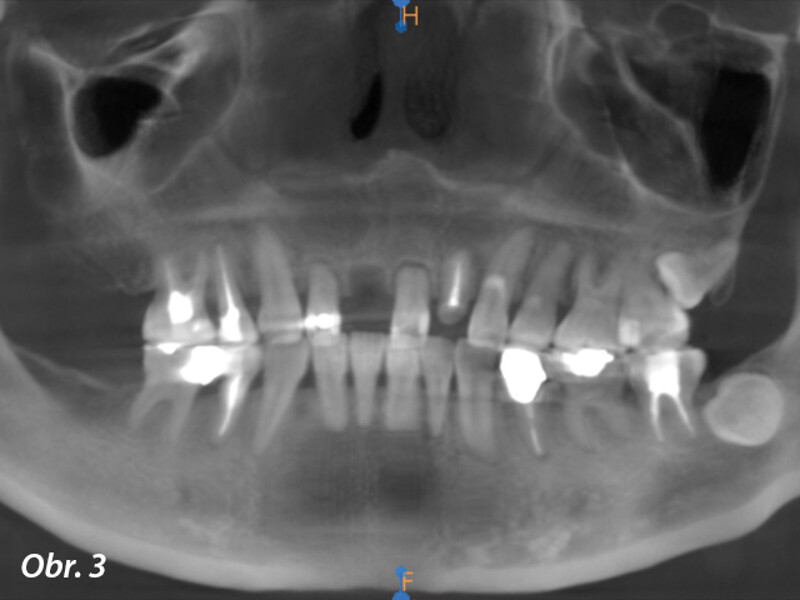

Okamžitá implantace a CADCAM